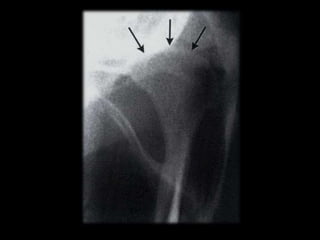

 Schüllers Technique

 Sagittal view of Lateral part of the condyle

and temporal components

 X-ray directed parallel to long axis of condyle

 Film is positioned against facial skin on side of

interest parallel to sagittal plane

 X ray tube head is projected from opposite side

 Central beam is projected downwards 25⁰ and

centered on T.M.J.

 Central beam is projected through cranium above

petrous ridge of temporal bone on film side

through T.M.J. in line with long axis of condyle

 Horizontal angle not more than 10⁰

 Vertical angle not more than 25⁰

Open mouth Closed mouth